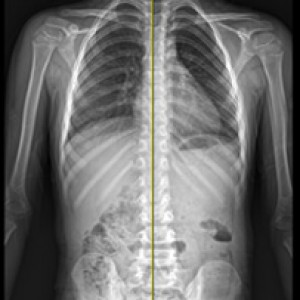

검사부터 다른 당당

“당당은 뼈만 보지 않습니다.”

근육과 근막의 정렬을 함께 진단하며, 풀 스파인 촬영을 통해 머리부터 모든 고관절, 발의 정렬까지 함께 파악하여 개개인에 맞는 전신 치료법을 설계합니다.

전신 엑스레이 검사

다리길이 엑스레이 검사

Before & After

해당 사진은 수정없는 실제 치료사진입니다.

환자의 치료결과는 환자의 상태, 치료방법 등에 따라 차이가 발생할 수 있습니다.